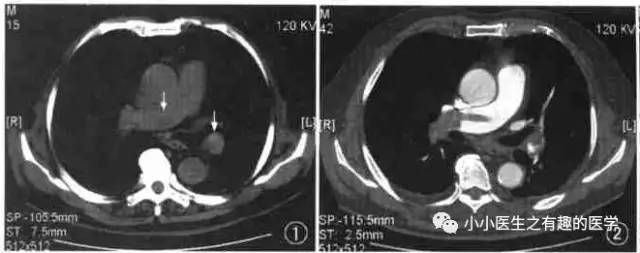

翠花上菜,学者上图。

发现嫌疑犯,立即逮捕。

增强CT对比,一目了然。

上面的病人,增强CT放大了。